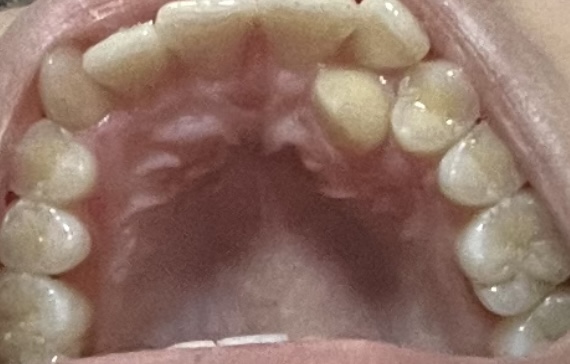

歯の裏側に歯が生えてしまっています。

抜歯か矯正どちらをした方がいいのでしょうか?

また矯正をする場合歯を抜くことなく矯正はできるのでしょうか?

右側にも歯列不正を認めますので矯正の方が良いと思います。

>矯正をする場合歯を抜くことなく矯正はできるのでしょうか?

抜歯症例だと思います。非抜歯では難しいと思います

写真拝見いたしました。

下顎の状態がわからないので矯正治療についてははっきりしませんが一番無難な方法は左側の犬歯を抜歯して右側の犬歯はそのままにしておくのがいいと思います。

矯正治療を考えるなら上額左右4番を(場合によっては下顎も)抜歯して矯正治療が可能かどうか診断してもらうのがいいように思います。

ただ矯正治療を選択した場合はかなり困難が予想されるので相当な覚悟が必要になります。